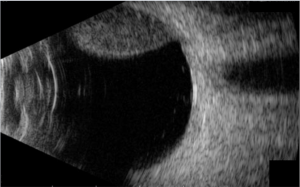

Based solely on physical examination and imaging, intraocular paragangliomas are difficult to distinguish from other types of metastatic disease or choroidal tumors, such as amelanotic choroidal melanomas. On fundoscopic exam for the cases reported, the most common finding was a non-pigmented or partially pigmented choroidal tumor with either concommitant retinal detachment or disturbance of overlying retinal pigment epithelium

Nonpigmented choroidal melanomas and intraocular paragangliomas can be difficult to distinguish as they can both clinically present as single-lobed masses with low internal reflectivity and subretinal fluid. Metastatic disease from extraocular origin should also be considered in the differential diagnosis, with biopsy as the only way to obtain a definitive diagnosis.